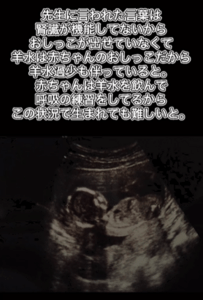

「胎児多発性嚢胞腎」と(@ymr_ymr_354さんより提供)

赤ちゃんは腎臓が十分に機能していないため尿を作ることができず、その影響で羊水が減少。羊水は肺の発達にも関わることから、出生後の呼吸が難しい可能性があると説明されました。

生まれても難しいと…(@ymr_ymr_354さんより提供)